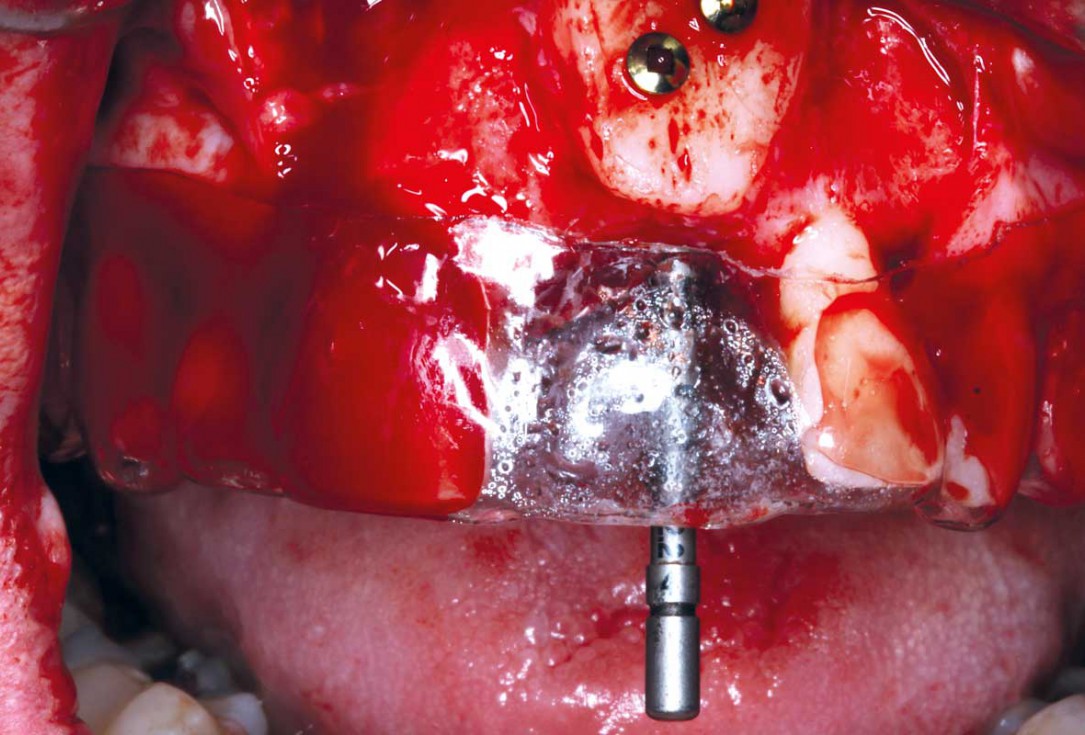

9/35 - Stabilisation of the bone block with two 10 mm fixation screws placed oblique. Sharp edges of the block were polished to avoid defeasance in the soft tissue healingBlock grafting in the aesthetic zone with maxgraft®, Jason® membrane and cerabone® - Dres. H. Maghaireh and V. Ivancheva

10/35 - Stabilisation of the bone block with two 10 mm fixation screws placed oblique. Sharp edges of the block were polished to avoid defeasance in the soft tissue healingBlock grafting in the aesthetic zone with maxgraft®, Jason® membrane and cerabone® - Dres. H. Maghaireh and V. Ivancheva